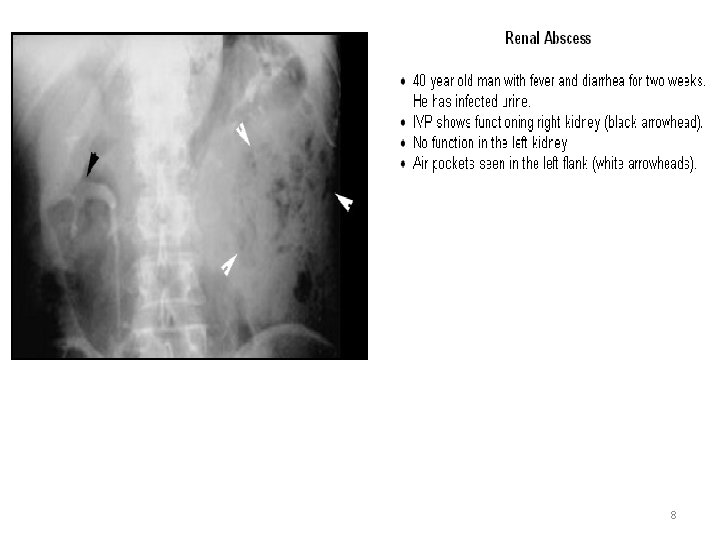

A, Enhanced CT scan shows an irregular septated low-density mass (M) extensively involving the left kidney. Note thickening of perinephric fascia) and extensive compression of the renal collecting system. Findings are typical of renal abscess. B, Ultrasound longitudinal scan demonstrates a septated hypoechoic mass (M) occupying much of the renal parenchymal volume 7

8